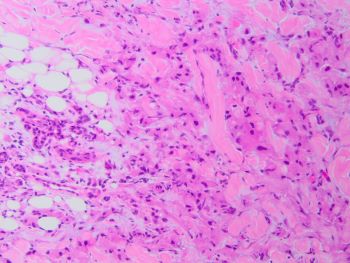

A 67-year-old male presents with a parotid mass associated with facial pain and cervical adenopathy. Fine-needle aspiration and core needle biopsy are performed and representative sections are shown.p63 immunostain is negative.

Brief explanation of the answer: The cytology smears show cells with oncocytic morphology and significant nuclear atypia. Histologic sections show pleomorphic tumor cells infiltrating as cords and nests. No keratinization or mucinous cells are noted. Salivary duct carcinoma is an important diagnostic consideration when encountering atypical oncocytic cells. This aggressive tumor typically affects older males and is associated with a poor prognosis. Tumor cells are positive for androgen receptor and GATA-3 and negative for myoepithelial markers. Some cases may also express Her2 by immunohistochemistry.